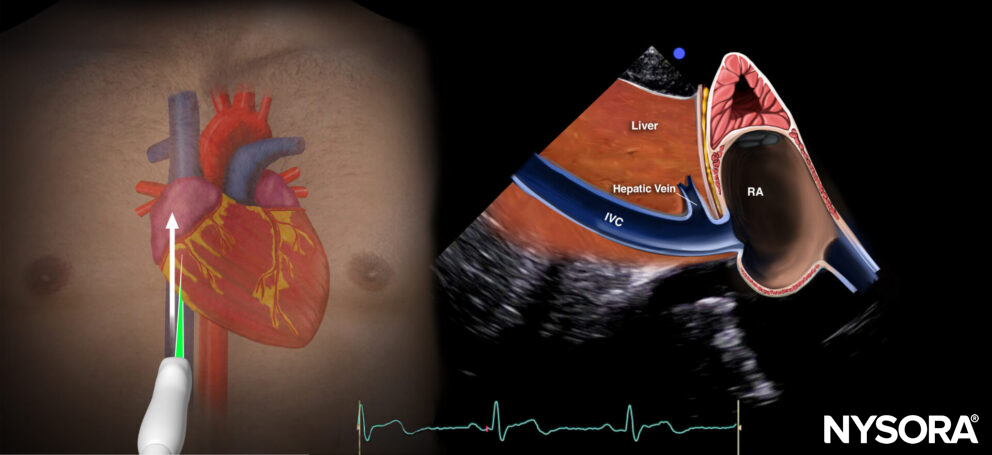

The inferior vena cava view cuts through the inferior vena cava and the right atrium.

Sonoanatomy of the inferior vena cava view. Inferior vena cava (IVC), right atrium (RA), hepatic vein(sometimes), liver.

Reverse ultrasound anatomy:

Reverse Ultrasound Anatomy of the inferior vena cava view. Inferior vena cava (IVC), right atrium (RA), hepatic vein(sometimes), liver

Practical use:

- Volume status (inferior vena cava size variation)

Tips

- Volume status assessment by inferior vena cava size variation is not reliable in cases of increased right ventricular pressure or volume overload, since this will also lead to a dilated inferior vena cava.

- The aorta runs parallel to the inferior vena cava. Distinguish the inferior vena cava from the aorta! The aorta is surrounded by white, fatty tissue, has an angle toward the patient’s dorsum, and is pulsatile.

- The inferior vena cava runs intrahepatically and has a hepatic vein branch. In case of a dilated inferior vena cava, the aspect of the inferior vena cava and the hepatic vein is sometimes compared to a ‘Moose head’ or a ‘Playboy bunny’.